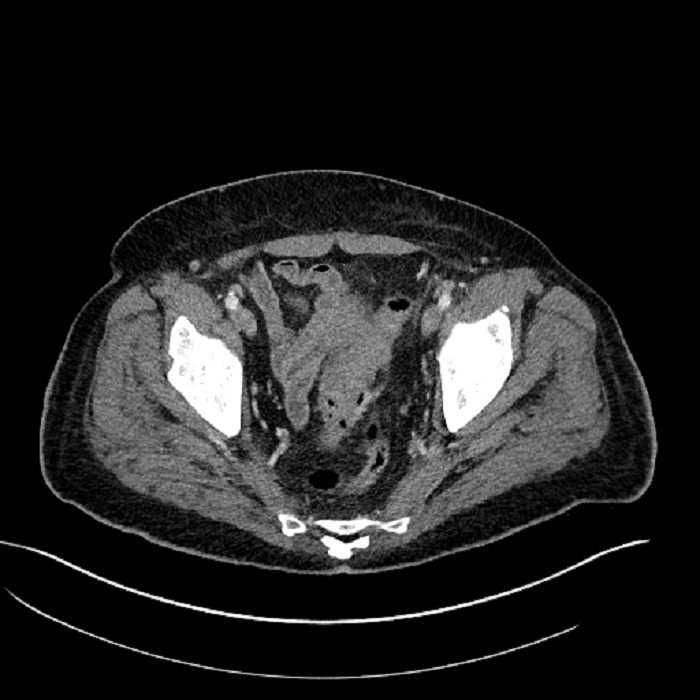

• Mild mural thickening of a segment of the sigmoid colon with adjacent fat stranding and a 1.5 cm fluid and gas collection along the tip of an inflamed diverticulum

• Loss of the normal fat plane between this collection and adjacent loops of small bowel, which demonstrate mural thickening

• High grade stenosis of the left common iliac artery, with the left internal and external iliac arteries remaining patent

Acute sigmoid diverticulitis complicated by a small contained perforation and a large abscess in the right hepatic lobe. Additional small subcapsular abscesses along the anterior margin of the left hepatic lobe.

Additionally, loss of the normal fat plane between the peridiverticular collection and adjacent thickened loops of small bowel raises the potential for an enterocolonic fistula.

High grade stenosis of the left common iliac artery. The left external and internal iliac arteries are patent.

Hepatic abscess showing the double target sign with low density internally surrounded by a thin inner enhancing rim (red arrow) and ill-defined outer low density rim (yellow arrow). Blue arrow indicates an internal septation. Red arrows: additional smaller subcapsular abscesses. Red arrow: focal contained perforation associated with diverticulitis.